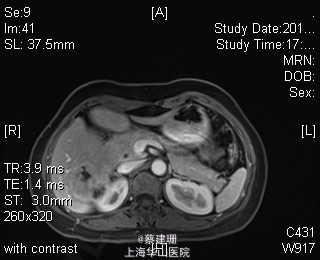

主诉:平滑肌肉瘤、肝转移癌术后,发现肝多发转移2月余。 现病史:患者3年前外院检查发现后腹膜肿瘤,外院行后腹膜肿瘤切除术后,术后病理为:平滑肌肉瘤,2013年12发现肝左叶转移癌,外院行肝左叶肿瘤切除术,术后病理为:梭行平滑肌肉瘤。2月余前患者复查发现肝脏多发转移,2015-4月肝脏MRI:肝脏多发转移。现患者无恶心、呕吐,无呕血、黑便,无皮肤巩膜黄染,无剧烈腹痛发作。现为进一步诊治收住入院。

查体:锁骨上淋巴结未扪及肿大;腹部平坦,可见陈旧性手术疤痕。未见肠型、胃型蠕动波,腹软,无压痛及反跳痛,无肌卫,肝脾肋下未及。Murphy’s 征(-),肝区叩击痛(-),肾区叩击痛(-);移动性浊音阴性。 辅查:2015-4月肝脏MRI:肝脏多发转移。

诊断 :1、多发肝转移癌 2、后腹膜平滑肌肉瘤术后 3、肝转移癌术后 处理:取右侧肋缘下切口,左侧延长,逐层切开进腹,探查腹腔:见上腹部粘连,仔细游离上腹部腹腔粘连,探查见无腹水,胃、肠、胰、脾及盆腔脏器未及异常,腹腔未见明显转移结节;肝脏无硬化。肝门淋巴结无肿大,门静脉主干无栓子。肿瘤多枚,最大两枚位于肝右叶VI段,肿瘤大小约7*6*5cm。V段肿瘤直径约5cm。左内叶肿瘤多枚,直径0.5-4cm,紧贴第一肝门。左外叶肿瘤多枚,直径1-3cm,肿块质韧,边界尚清,有包膜。术中诊断为转移性肝癌,决定行左半肝切除,肝右叶特殊肝段切除。